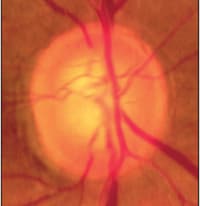

Optic nerves can develop glaucoma in many different ways. Concentric cupping is a common pattern of glaucomatous damage (Figure 2) where the optic nerve loses just some rim tissue everywhere. Very often this kind of disc damage occurs in eyes with high intraocular pressure and yet since the damage is diffuse, the visual fields can remain normal despite significant rim loss. There is extensive literature, particularly described by Quigley, demonstrating that you can lose up to half the optic nerve axons before you see a visual field defect, and that is particularly true with concentric cupping.

Figure 2. Concentric cupping, a common pattern of glaucomatous damage.